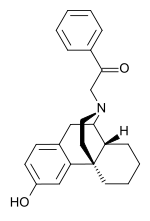

The pharmacodynamic response to an opioid depends upon the receptor to which it binds, its affinity for that receptor, and whether the opioid is an agonist or an antagonist. For example, the supraspinal analgesic properties of the opioid agonist morphine are mediated by activation of the μ1 receptor; respiratory depression and physical dependence by the μ2 receptor; and sedation and spinal analgesia by the κ receptor. Each group of opioid receptors elicits a distinct set of neurological responses, with the receptor subtypes (such as μ1 and μ2 for example) providing even more [measurably] specific responses. Unique to each opioid is its distinct binding affinity to the various classes of opioid receptors (e.g. the μ, κ, and δ opioid receptors are activated at different magnitudes according to the specific receptor binding affinities of the opioid). For example, the opiate alkaloid morphine exhibits high-affinity binding to the μ-opioid receptor, while ketazocine exhibits high affinity to ĸ receptors. It is this combinatorial mechanism that allows for such a wide class of opioids and molecular designs to exist, each with its own unique effect profile. Their individual molecular structure is also responsible for their different duration of action, whereby metabolic breakdown (such as N-dealkylation) is responsible for opioid metabolism.

Several semi-synthetic opioids were developed in Germany in the 1910s. The first, oxymorphone, was synthesized from thebaine, an opioid alkaloid in opium poppies, in 1914.[228] Next, Martin Freund and Edmund Speyer developed oxycodone, also from thebaine, at the University of Frankfurt in 1916.[229] In 1920, hydrocodone was prepared by Carl Mannich and Helene Löwenheim, deriving it from codeine. In 1924, hydromorphone was synthesized by adding hydrogen to morphine. Etorphine was synthesized in 1960, from the oripavine in opium poppy straw. Buprenorphine was discovered in 1972.[228]

Morphinan derivatives